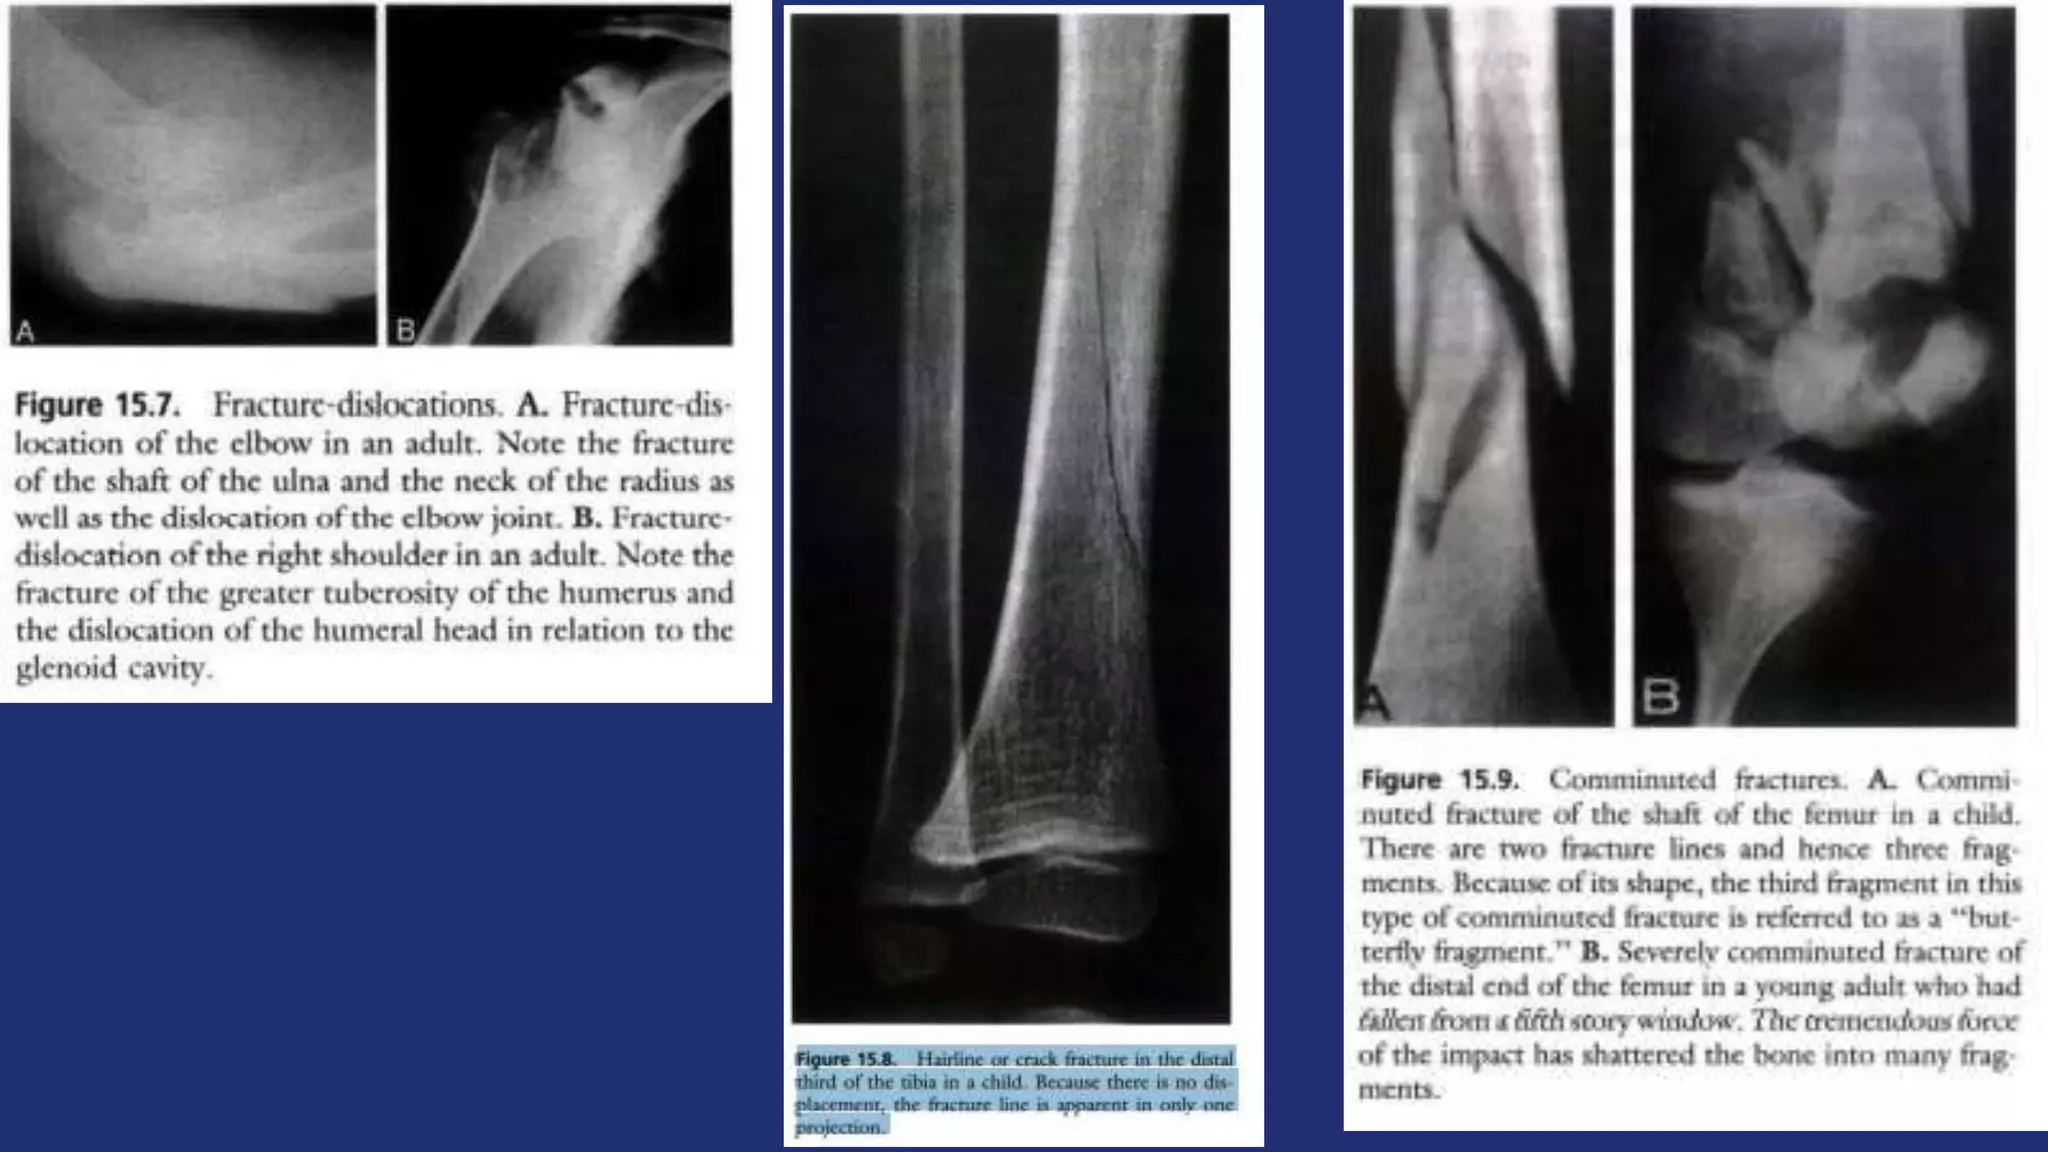

• Fracture-dislocation: dislocation is accompanied by an

intraarticular or extraarticular fracture

 Extent – complete, incomplete (hairline/crack, buckle, greenstick)

 Configuration – transverse, oblique, spiral, comminuted